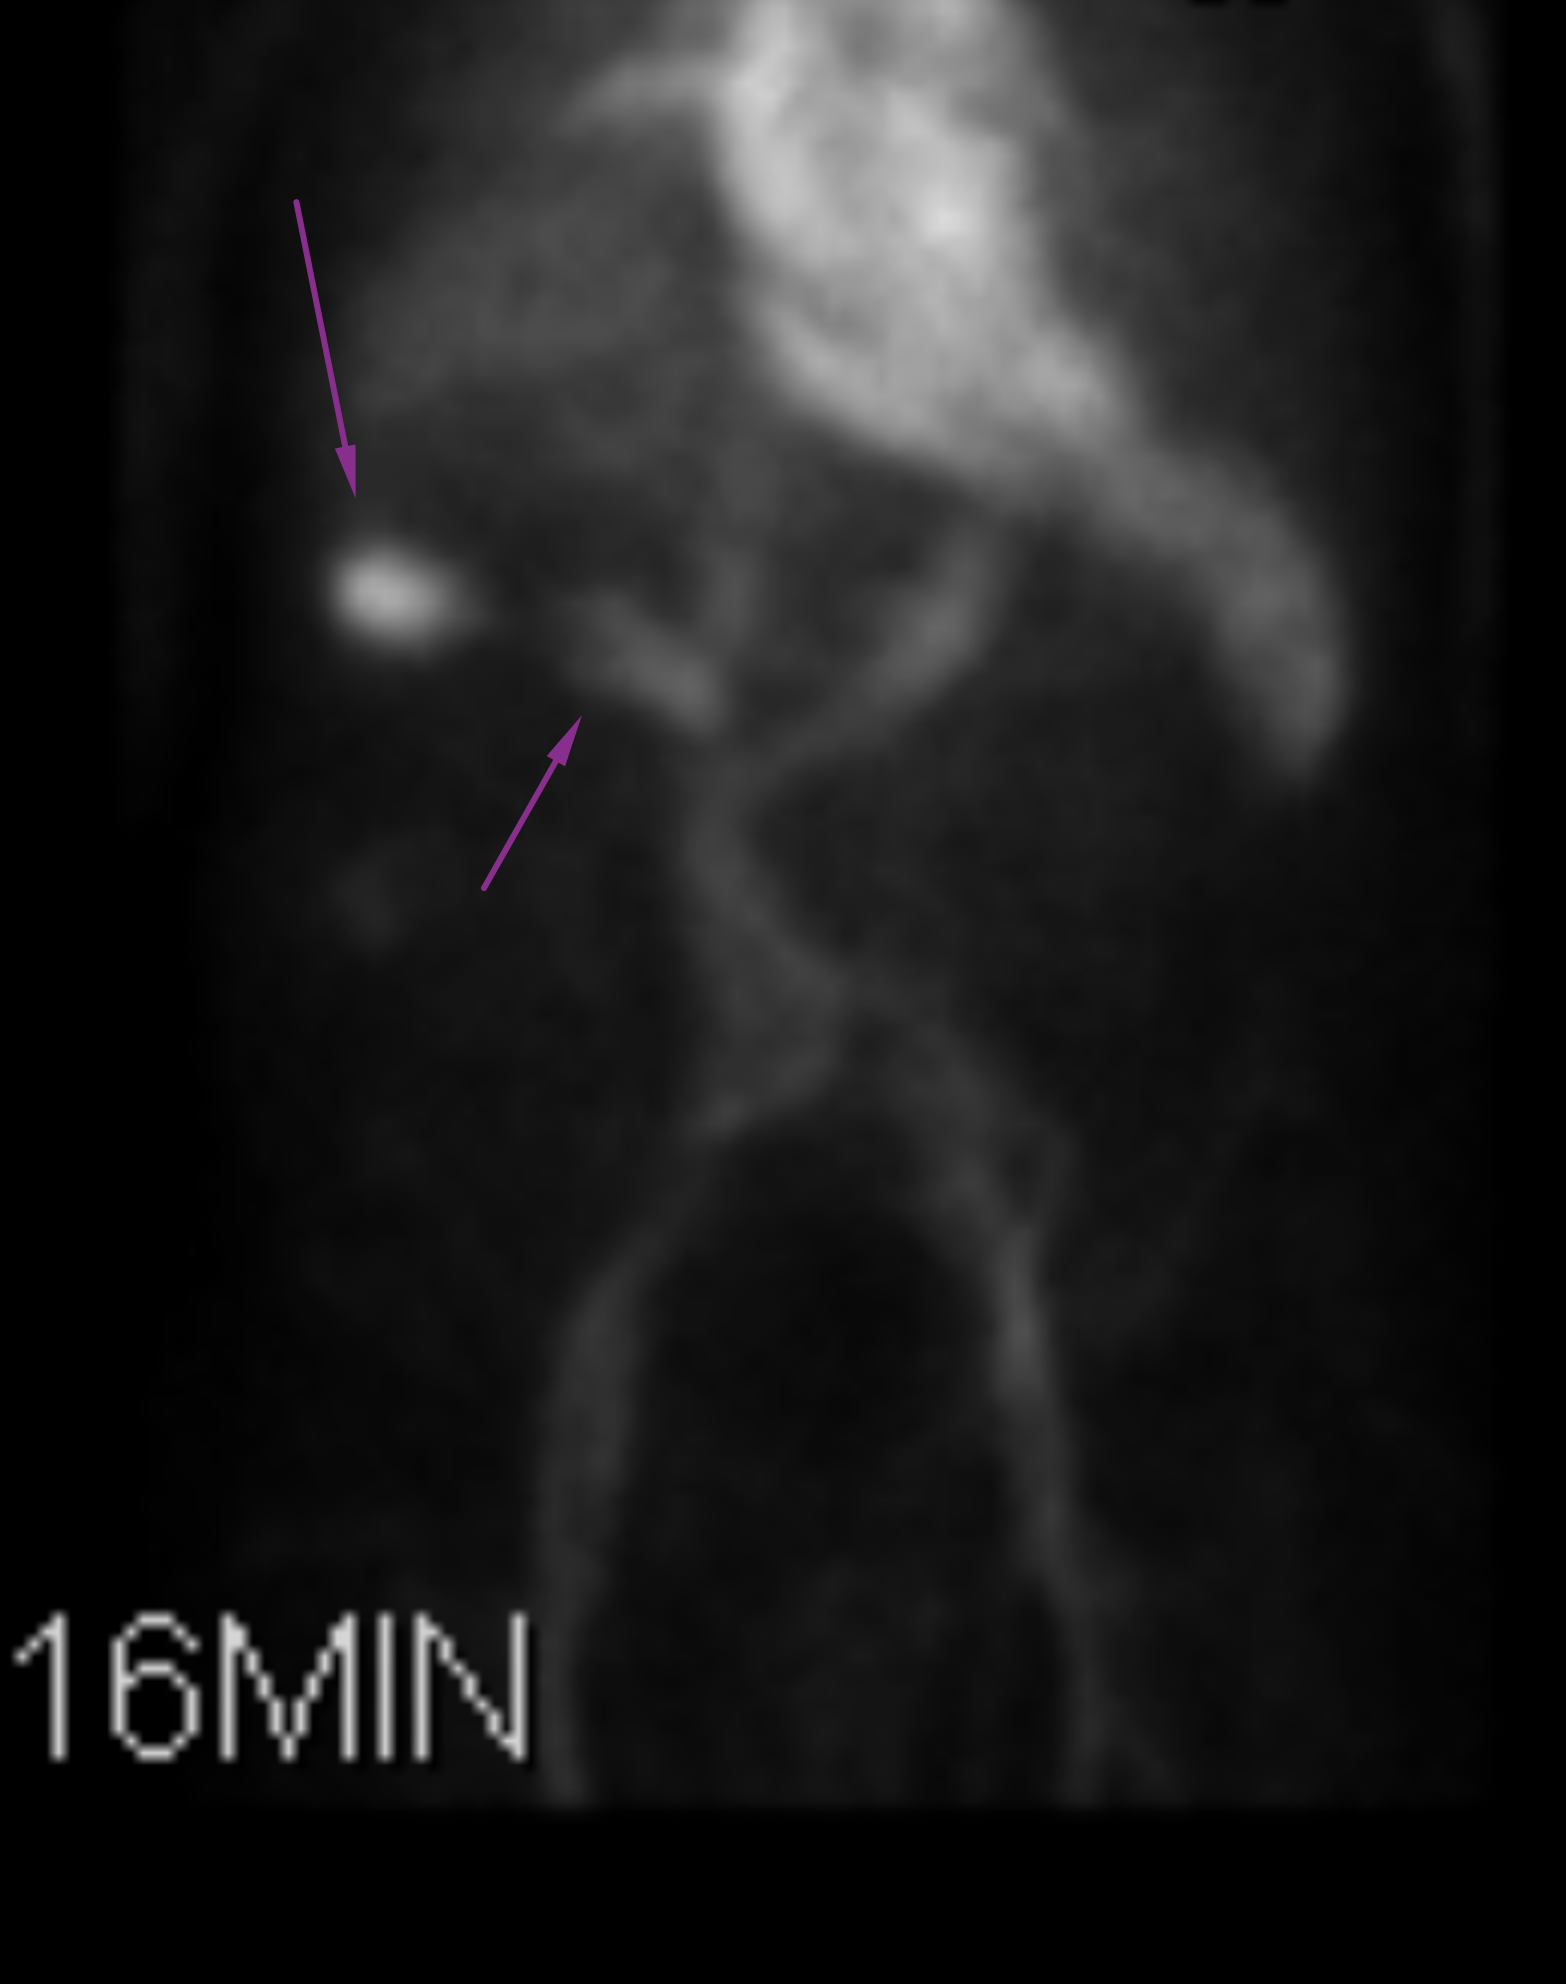

Age: 92

Sex: Male

Indication: Hematochezia

Radiotracer: Tc99m labeled RBCs

Sample ReportPositive for active GI bleed, likely originating in the hepatic flexure of the colon.